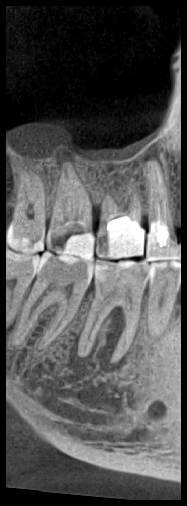

КТ от 28.05.2024

28_05.24(2).jpg.0ffa1febe861106733e1de830afbe6f4.jpg28_05.24-1(2).jpg.9c45d7be16aeed505bd413ce9bc6e69e.jpg28_05.24-2.jpg.a728a7d7e6213c1c8302b43adc89e4d0.jpg28_05.24-4(2).jpg.ac43f3448a3988c7006f74e1d0ce09da.jpg28_05.24-6(2).jpg.dd1fd85c6cc0fcd3d43bd9e71fc0d616.jpg28_05.24-8(2).jpg.885c8cb905445e9308f124fb9e5c616b.jpg28_05.24-9(2).jpg.6cceaaaa1b56d0967482c87b951fbe2d.jpg28.5.24-5(2).jpg.b2d79427a16769c9fd4f0d0911a9db8f.jpg28.5.24-7(2).jpg.f6c17f9820e72dc2708955a65a190b57.jpg28.0524-3(2).jpg.0aa9f153071766a340b428158a94ade8.jpg